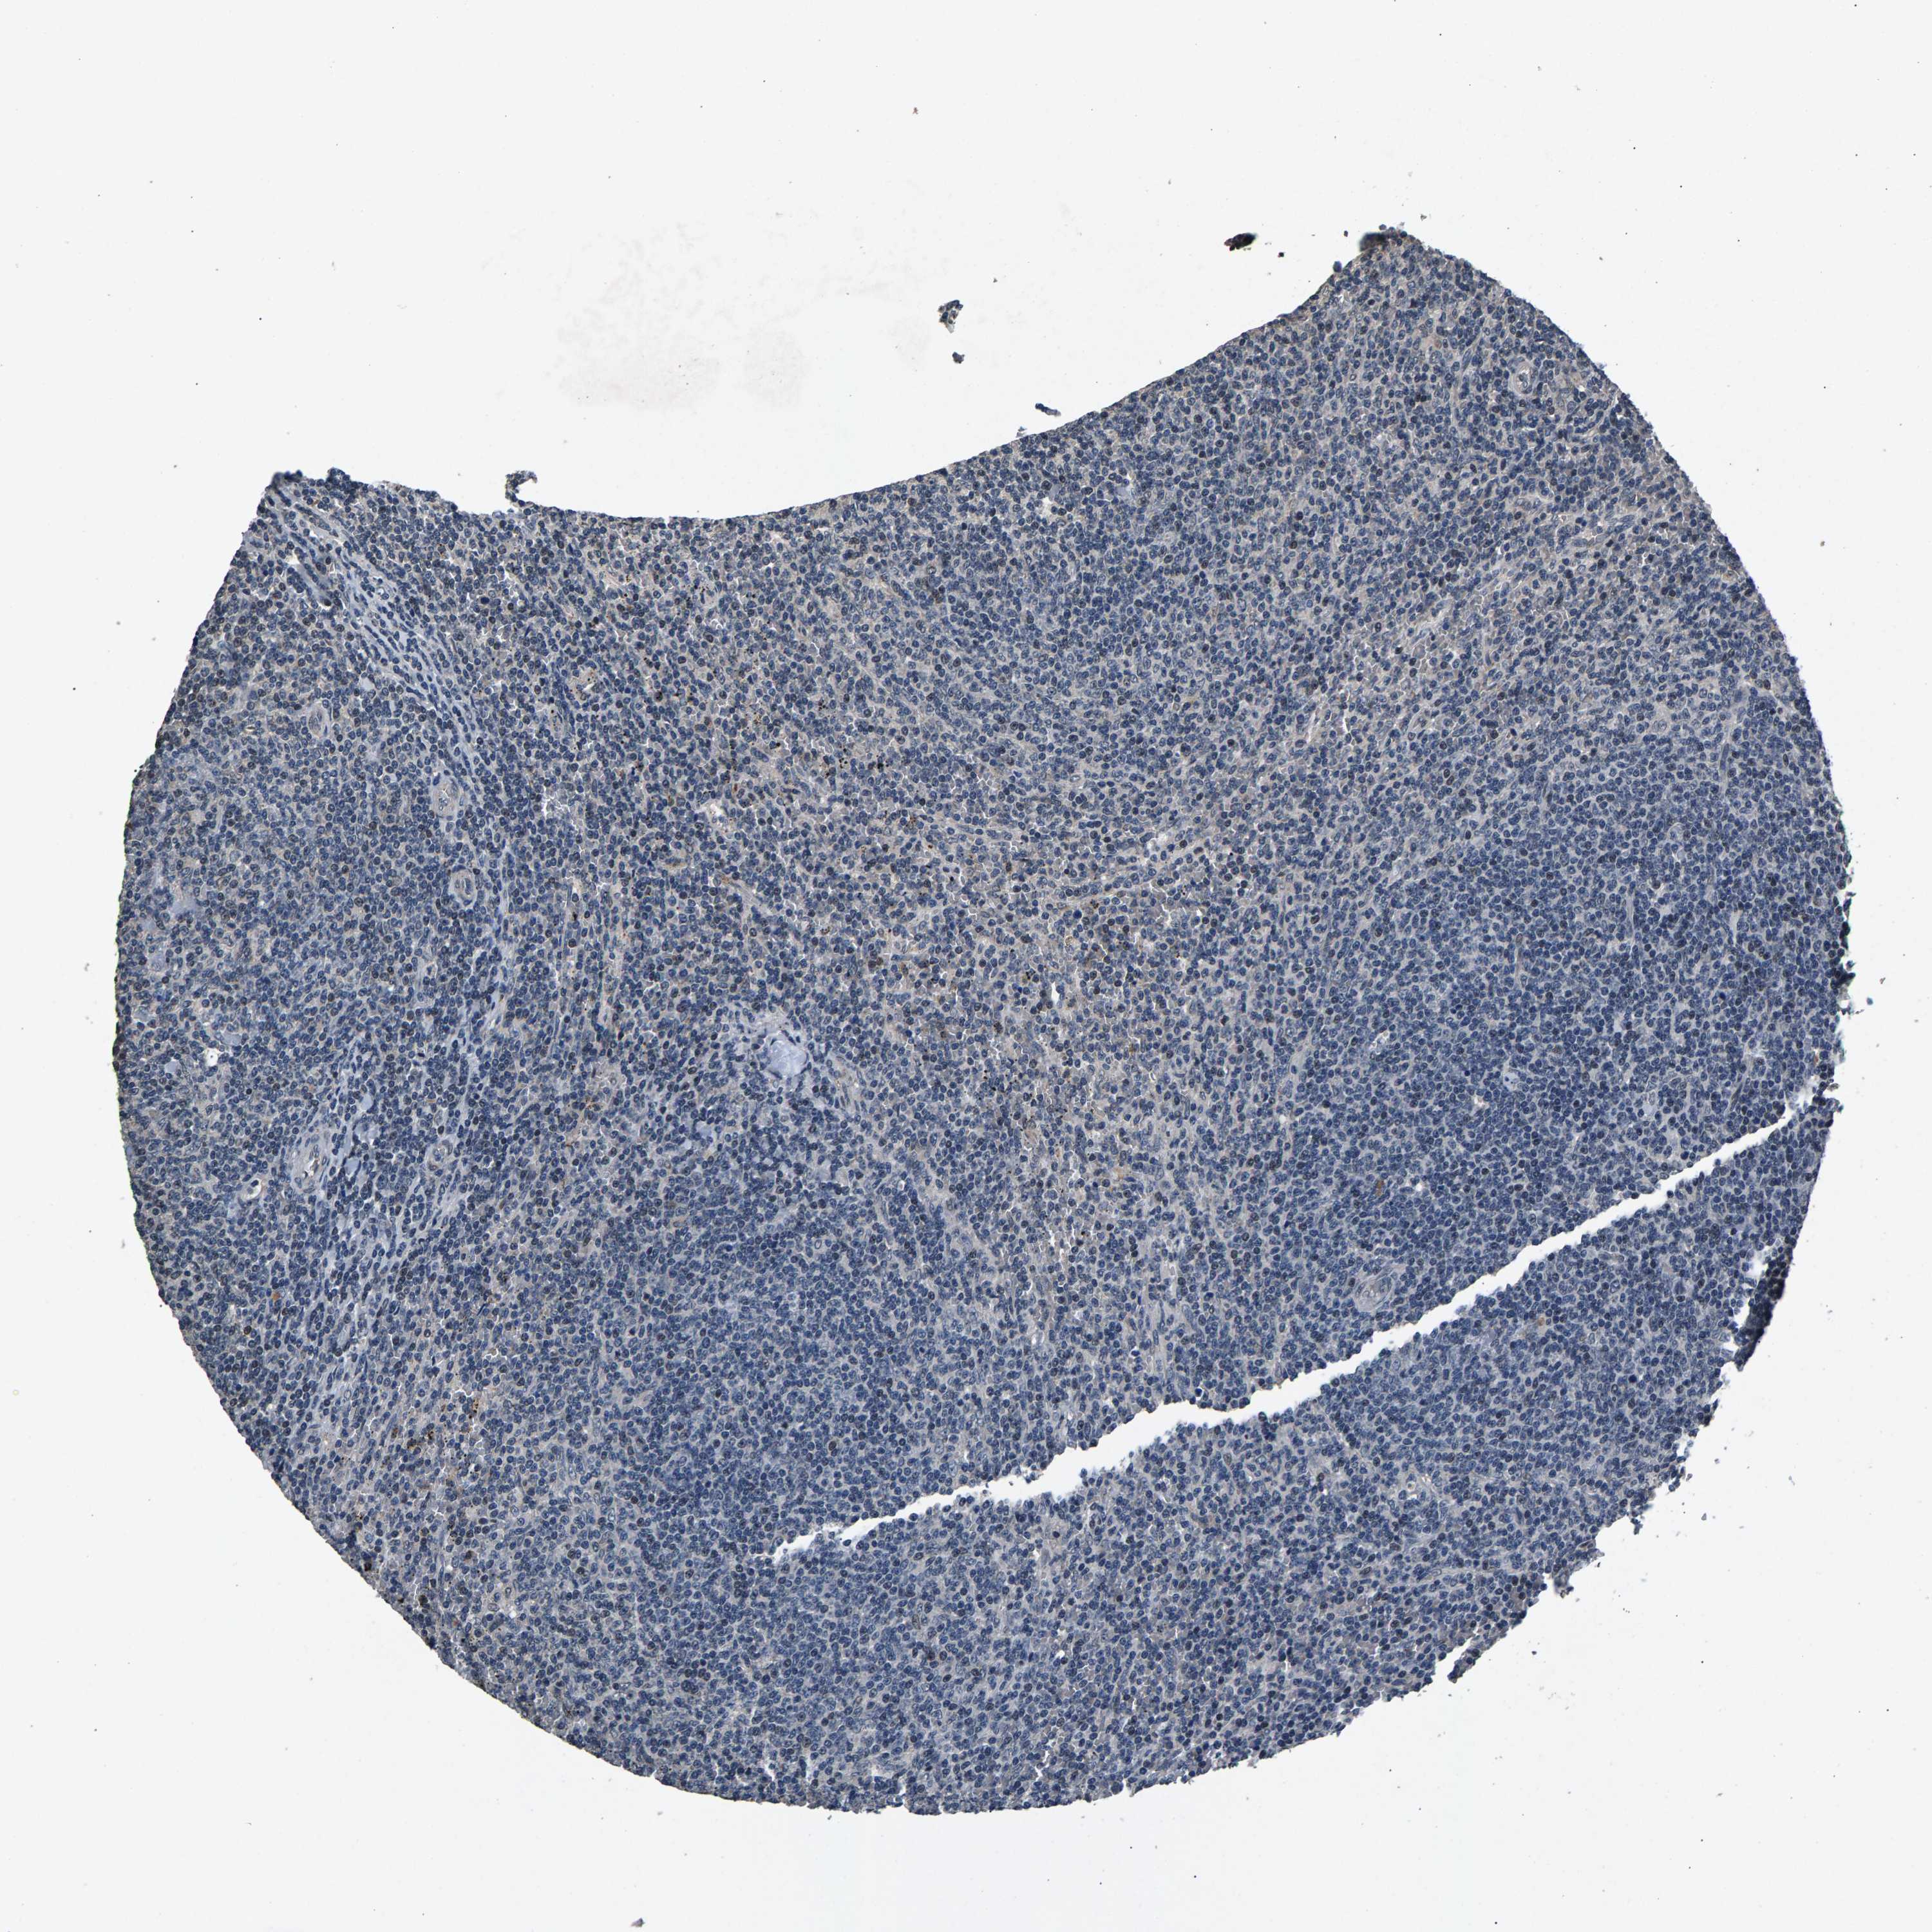

CANCER LYMPHOMA Show tissue menu

LYMPHOMA - Protein expressioni

A mouse-over function shows sample information and annotation data. Click on an image to view it in a full screen mode. Samples can be filtered based on level of antibody staining by selecting one or several of the following categories: high, medium, low and not detected. The assay and annotation is described here.

Each image is clickable and will lead to virtual microscopy that enables deeper exploration of all samples and also displays staining intensity scores, fraction scores and subcellular localization as well as patient and tissue information for each sample.

Antibody HPA019232

Antibody HPA021497

Antibody HPA021768

Hodgkin's disease, NOS

Malignant lymphoma, non-Hodgkin's type, High grade

Malignant lymphoma, non-Hodgkin's type, Low grade